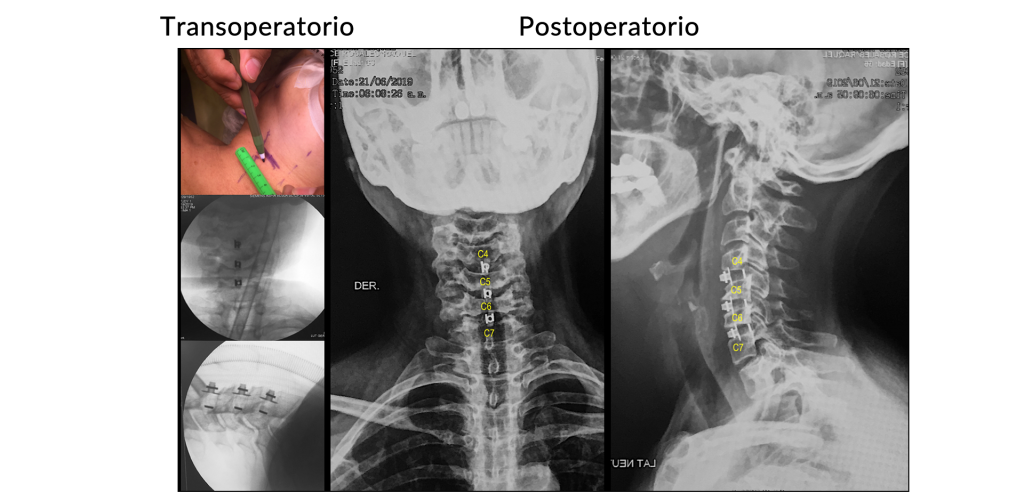

Inestabilidad de columna cervical